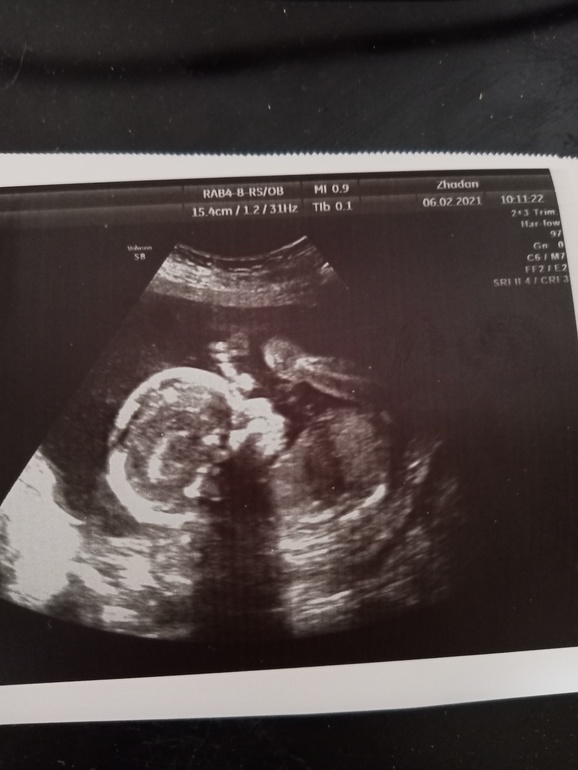

2 скрининг 19+6

Ура! Прошла сегодня 2 скрининг, девчулечка наша развивается в срок. И да, нам подтвердили пол🥰

Положение сейчас поперечное, я и чувствую шевелюшки то с с одного боку, то с другого.

Все очень подробненько измерили (мозг, сердечко, почки, желудок, печень, мочевой, артерии, легкие). Вес не писали.

Плацента 0-1 степени зрелости, 34мм от внутреннего зева. ШМ 39мм, внутренний зев закрыт. Высота столба околоплодных вод 55мм

Наша красоточка лежит согнувшись пополам, коленками доставая до подбородочка))